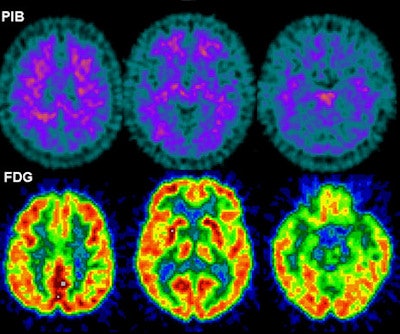

FDG-PET was used to detect glucose metabolism in the brain, while PiB-PET was used to detect amyloid deposition. Both tracers are commonly used in normal elderly people to assess the risk of developing Alzheimer's; however, they had not been used to determine a relationship between Alzheimer's and sleep-disordered breathing in this population.

To determine a correlation between sleep apnea and Alzheimer's, the researchers measured standardized uptake value ratios (SUVRs) in different regions of the brain using the FDG-PET and PiB-PET images. The brain areas included the middle temporal lobe, inferior parietal lobule, lateral temporal lobe, posterior cingulate cortex/precuneus, prefrontal cortex, occipital cortex, and thalamus.

The resulting SUVRs (see chart) suggest an association between sleep-disordered breathing and glucose hypometabolism in regions of the brain vulnerable to Alzheimer's disease, "which may indicate increased risk for Alzheimer's in cognitively normal elderly," according to the authors. Also, while the whole brain was hypometabolic, the effect was stronger in Alzheimer's-vulnerable regions.

"What you see are the areas that are usually vulnerable for Alzheimer's, such as the middle temporal lobe or the prefrontal cortex," Osorio said. "If the person is going to develop Alzheimer's, those areas start to show hypometabolism years before disease onset."